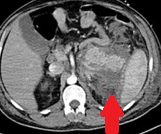

CT κοιλίας. Κόκκινο βέλος – Παγκρεατίτιδα – Περιπαγκρεατική συλλογή στον σπληνονεφρικό χώρο (Ευγενική παραχώρηση Dr. V. Penopoulos)